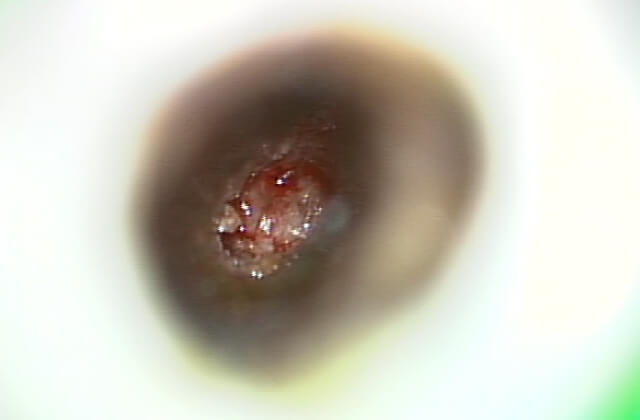

マイクロスコープで歯の内部を確認

(マイクロスコープを使うと歯の中に神経のある管が存在している事が分かります)